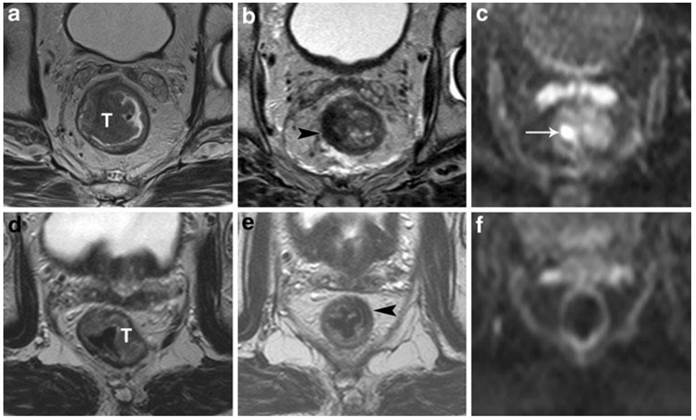

Lambregts et al. studied a total of 120 patients with locally advanced rectal cancer from three university hospitals who underwent chemoradiation therapy followed by standard T2 weighted-MRI and diffusion weighted imaging (DWI) (Figures 4 and 5). The sensitivity for selection of complete responders ranged from 0-40% on standard MRI versus 52-64% after the addition of DWI. They concluded that MRI+ DWI could significantly improve sensitivity for selection of complete responders.39 Furthermore, specificity is greater than 90%, which indicates that the risk for underestimation of residual tumor can be brought to <10%. As an adjunct to clinical tools (i.e., DRE, endoscopy, and biopsy), the combined use of MRI +DWI seems promising to enable a more precise selection of patients eligible to undergo less invasive treatments. The current results are obviously still premature for clinical decision-making, but its promise warrants further large and prospective patient studies.

Figure 5

StandardT2-weighted images of two patients with a tumor (T) in the rectum before (a, d) and after chemoradiation treatment (b,e). In the upper patient there is still a clear high signal intensity area on DWI (arrow in c), which was confirmed to be a pT2 residual tumor at histology. In the lower patient, no high signal is shown on DWI (f) and a complete tumor response (pT0) was confirmed at histology. Courtesy of Lambregts, et al. 39